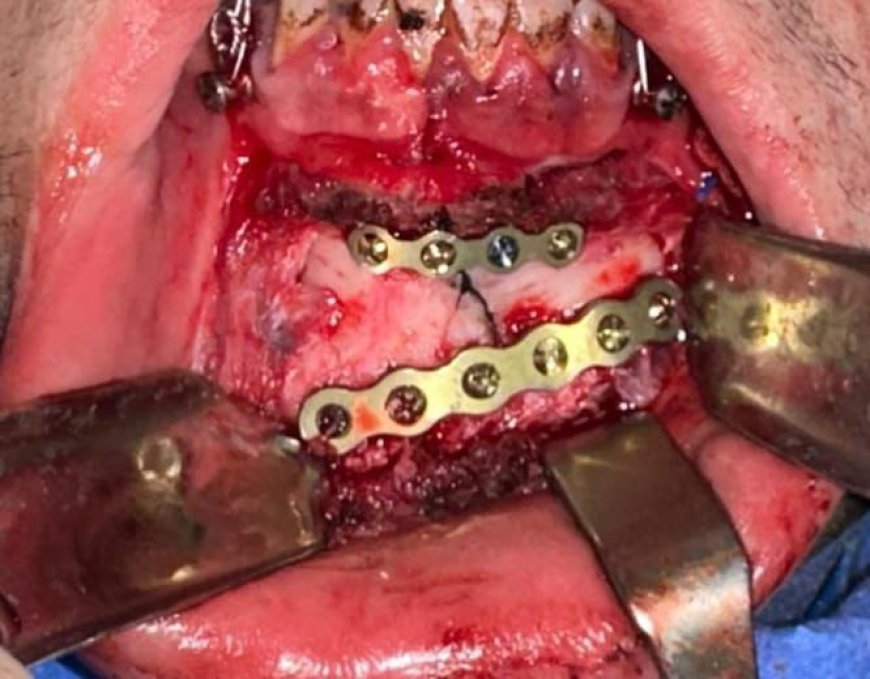

وفي هذا السياق، نجح الفريق الطبي بمستشفى عين شمس العام في إجراء جراحة دقيقة للوجه والفكين لإحدى الحالات المصابة إثر حادث سير، تم تثبيت كسر الفك السفلي تحت تأثير التخدير الكلي، في تدخل جراحي دقيق أسهم في استقرار الحالة وتحسين فرص التعافي.